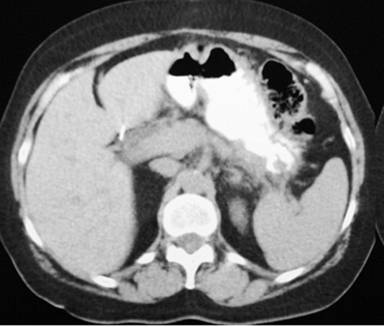

The diagnosis of pancreatic pseudocyst was highly probable but, considering the uncommon chronic presentation, and, in order to measure amylase, tumor marker CA 19-9 and carcinoembryonic antigen levels (CEA) in the cystic fluid, an image-guided puncture was planned. To demonstrate possible communication between the pseudocyst and the main pancreatic duct, an endoscopic retrograde cholangiopancreatography (ERCP) was planned as well but, since the patient was reluctant to undergo both procedures, surgical drainage was carried out instead. Since the pseudocyst appeared to be adherent to the posterior gastric wall on CT scan, a cystogastrostomy was scheduled. At laparotomy, by means of an anterior gastrotomy and a 5 cm incision using electrocautery at the posterior gastric wall, where the bulging pseudocyst was visualized, abundant non-viscous clear brownish fluid was drained immediately. A fluid sample and pseudocyst wall biopsy were sent for determination of amylase level and histopathological exam. The amylase fluid level was 8,524 IU/L. The cystogastrostomy was completed using a running 2-0 polypropylene suture. The anterior gastrotomy was sutured as was the abdominal wall. Both frozen section and definite histopathological examination demonstrated fibrous tissue, with no epithelial lining, epithelial tissue or malignant transformation. With an uneventful recovery, the patient was discharged 10 days after surgery. At follow-up 12 months later, an abdominal wall protrusion was noted upon exertion. An abdominal wall defect was palpated at the surgical scar. A control CT scan demonstrated a midline abdominal wall defect, but no evidence of a pancreatic pseudocyst (Figures 2 and 3). Incisional hernia surgery was performed. Six months after this latter surgery, the patient remains in good condition.

Figure 2. Pancreatic CT scan with absence of a pseudocyst. |